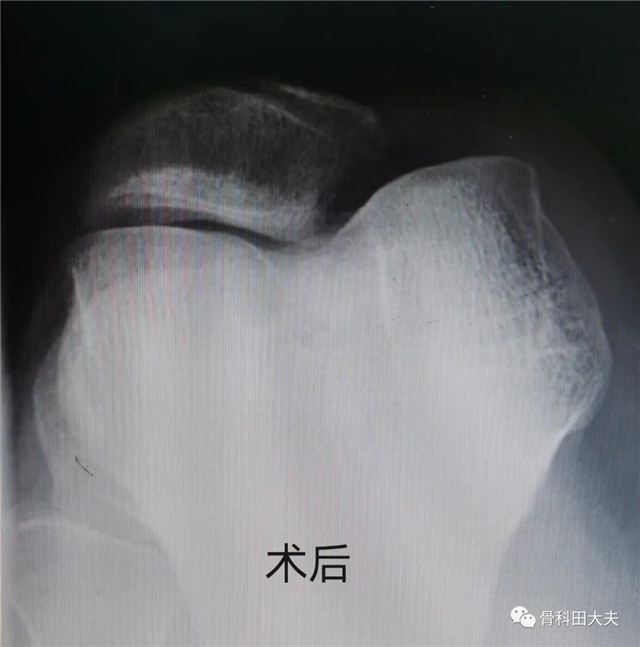

患者婷婷是一名十七岁的高中生,做广播操跳跃落地时扭伤右膝,伤后肿胀疼痛活动受限,就诊于长治二院运动医学科,经仔细询问病史、查体后诊断为“复发性髌骨脱位”。该患者已经不是第一次发生这种情况了,既往已经有过三次类似的情况了。并且受伤时自己明确的感觉到“膝盖骨(髌骨)”向外“跑出去了”。患者的家长很疑问,为什么跳了一下就会髌骨脱位呢? 很多人认为关节脱位 是需要很大外伤力量的 所以当被诊断为 “髌骨脱位”时 心中会有无数个问号 通常情况下,第一次发生髌骨脱位,可以采取保守治疗,如果髌骨脱位反复发生,有些患者一年甚至可以髌骨脱位十余次,临床上就诊断为“复发性髌骨脱位”,往往需要手术治疗。上述患者婷婷就是这种情况,经过手术治疗(内侧髌股韧带重建术),婷婷已经痊愈,术后至今已经6年,术后髌骨脱位没有再发生。 但是如果有以下情况,即便是第一次发生“髌骨脱位”,也可能需要手术治疗。第一,髌骨脱位的同时发生了软骨剥脱或者撕脱性骨折,第二产生了游离体,第三有明确的韧带等重要结构的断裂损伤(如内侧髌股韧带英文缩写MPFL)。 科室推荐 长治二院运动医学病区致力于运动损伤的研究、治疗已有十余年,治愈患者已数千例,在李晓东院长带领下,目前是长治地区唯一拥有独立运动医学病区的医院,拥有专业的运动医学医护团队,年手术量500例以上,稳居长治第一,省内前列。诊疗范围包括膝、肩、踝、髋等各关节运动损伤疾病。 微创关节镜技术是运动医学一大特色。在关节运动损伤手术治疗中占有非常重要的地位。该手术技术微创、手术视野清晰、处理病变彻底、术后恢复快、疗效好,具有传统切开手术无可比拟的优势。 膝:游离体、半月板损伤、交叉韧带及内外侧副韧带损伤、韧带撕脱骨折、髌骨脱位、骨性关节炎、膝关节不稳定、剥脱性软骨炎、滑膜软骨瘤 肩:肩关节脱位不稳、肩锁关节脱位、肩袖损伤、大结节骨折、肩盂唇损伤、肩撞击综合症、冻结肩、钙化性肌腱炎、游离体、肱二头肌断裂/脱位 踝:前后撞击综合症、距骨骨软骨损伤、踝关节不稳、侧副韧带损伤、踝关节炎、色素绒毛性滑膜炎、游离体、撕脱骨折、跟腱断裂、腓骨肌腱脱位等 髋:撞击综合症、盂唇损伤、滑膜软骨瘤、游离体以及各部位肌肉、肌腱、韧带损伤 0355-3126023 供 稿丨田海泉 编 辑丨卞 晨 审 核丨雷 赫